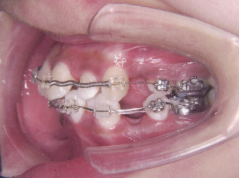

ステップ7.治療開始

装置装着前

装置装着後

※治療期間について

元の歯ならびの状態にもよりますが、

通常約1年から2年ぐらいです。